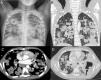

Granulomatosis linfomatoide: una enfermedad linfoproliferativa infrecuente en la edad pediátrica

Lymphomatoid granulomatosis: a rare lymphoproliferative disease in the pediatric age